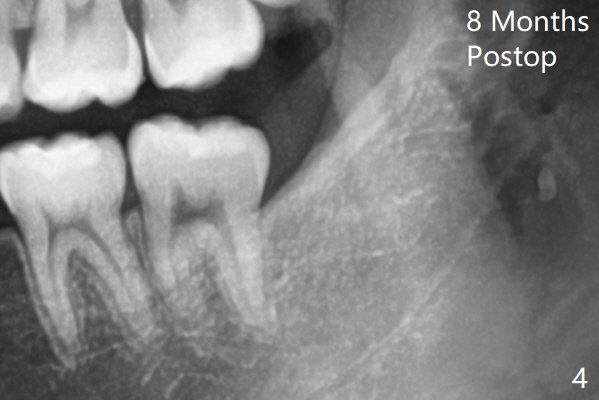

1.5年智齿牙根长长(图二)。1.5月后下颌智齿拔除放置Osteogen Plug(图三)。八个月后牙槽窝愈合(图四)